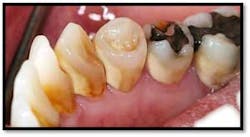

UL/LL reflected in a mirror and UL/LL radiograph

Treatment: FM Perioscopy completed in two, 2-hour sessions with local anesthetic and micro ultrasonics. No hand instruments are necessary during Perioscopy.

Note: When instrumenting “blindly,” the end point is unknown and debris is left behind. Visualization via the Perioscopy System ensures effective treatment is rendered because the bioburden is completely removed. Ultrasonic instrumentation is not only effective and efficient for thorough bacterial removal, but is an easier therapy to tolerate for the patient, with less sensitivity post treatment.9 months Post Treatment: